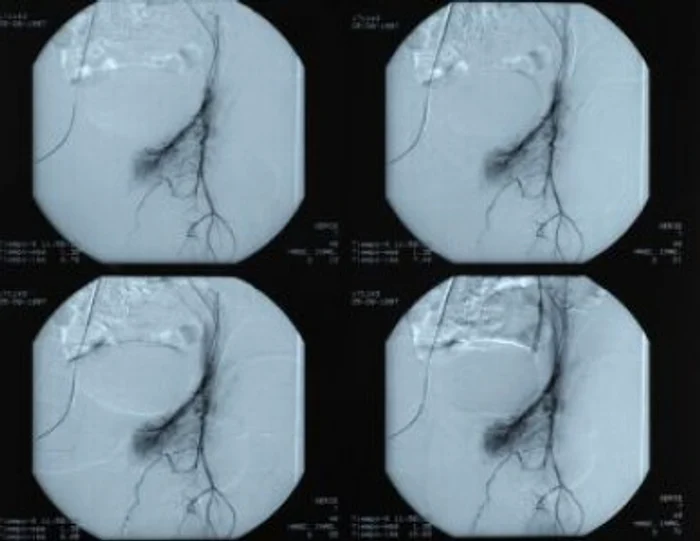

Arteriografia este utilă pentru depistarea unei îngustări arteriale, a unui anevrism sau pentru a afla sursa unei sângerări digestive. Cu ajutorul ei mai pot fi identificate eventuale malformaţii ale vaselor, leziuni traumatice. Mai poate indica locul în care circulaţia sângelui este întreruptă sau diminuată din cauza trombozei arteriale sau venoase.

Procedura constă în injectarea într-o arteră a unei substanţe de constrast pe bază de iod, care va străbate venele şi arterele. Analiza nu produce durere, deoarece se realizează sub anestezie locală şi durează între 10 minute şi 2 ore, în funcţie de complexitatea ei.

Există 2 tipuri de arteriografii: cea globală, care implică injectarea substanţei de contrast într-un trunchi arterial, şi cea selectivă, când substanţa este injectată într-o singură arteră, cum este cea renală.